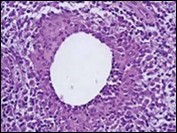

Core needle biopsy of idiopathic granulomatous mastitis enunciates multiple aggregates of non- caseating epitheloid cell granulomas within and encompassing breast lobules, constituted of epitheloid histiocytes, lymphocytes, neutrophils and multinucleated giant cells. Granulomatous inflammation is predominantly lobulo-centric. The inflammation is preponderantly composed of lymphocytes, plasma cells, epitheloid histiocytes, multinucleated giant cells and neutrophils. Neutrophils can configure micro-abscesses and encompass vacant micro-cystic cavities, morphological features which are in common with cystic neutrophilic granulomatous mastitis. Non specific lobulitis along with a lymphoid and plasma cell infiltrate accompanies the granulomatous inflammation. Necrosis is usually absent. Neutrophilic micro-abscesses can be accompanied by fistula formation 4, 5.

Multinucleated giant cells are detected in an estimated three fourths (78.5%) instances. Plasma cells are discernible in around half (53.9%) of the subjects and usually appear at the margins of cystic vacuoles with centric accumulation of neutrophils within the granulomas.

Figure 3.Granulomatous mastitis with scattered langhans and foreign body giant cells, epitheloid cell granuloma and lymphoid ingress11.